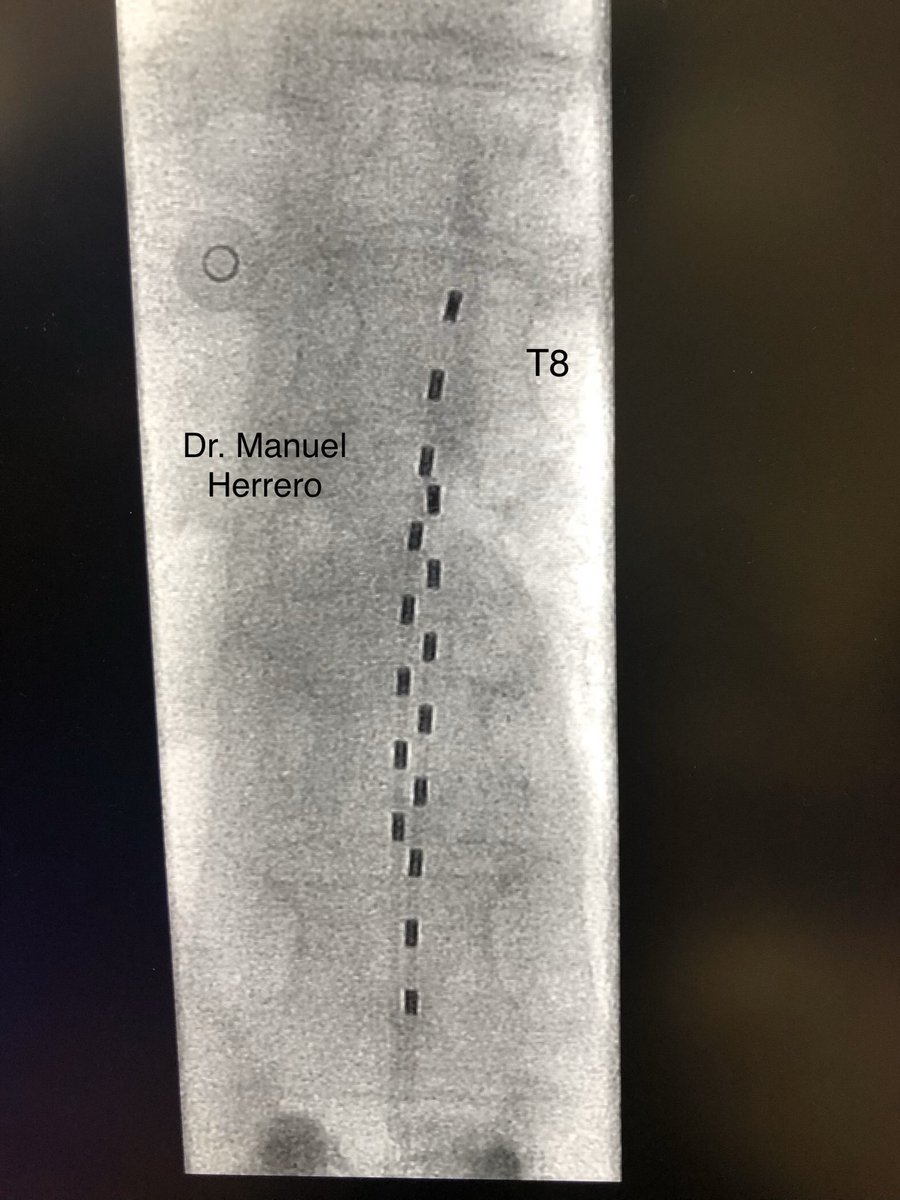

New challenge: difficult approach to the epidural space due to many vertebral cementations and L1 fracture that invades the spinal canal.

#spinalcordstimulation#chronicpain#lowbackpain#highfrequency@Nevro_HF10@primendocirugia@HMHOSPITALESpic.twitter.com/0ahELsyMhR